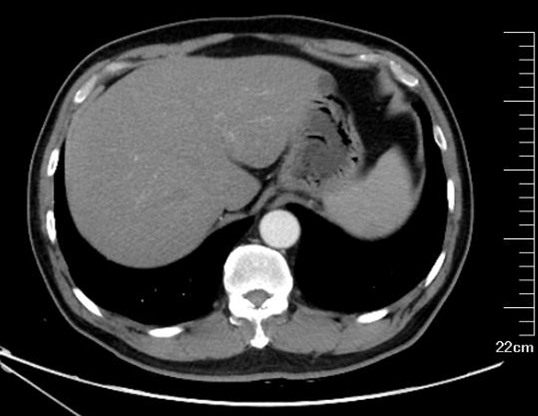

为进一步排查发热原因,寻找潜在感染灶,予胸腹盆部增强CT,结果提示:两肺感染,两肺上叶为著,较前稍进展;甲状腺左叶结节灶;脂肪肝,肝囊肿;肝左外叶稍低密度灶:不典型血管瘤?其他?双侧肾上腺结节样增生;左侧肾盂旁囊肿可能,左肾微小结石;前列腺钙化。心脏彩超:左室壁部分心内膜面及部分乳头肌回声增强,心包少量积液,三尖瓣轻度反流(图2,图3)

图2  胸部CT两肺感染,两肺上叶为著,较前稍进展

图3  腹部增强CT肝左外叶稍低密度灶